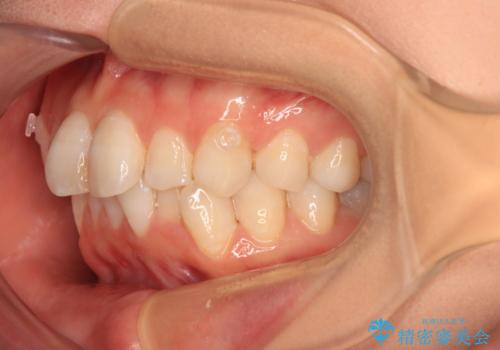

- 上下前歯のデコボコを改善したいとのことで来院された患者様です。

マウスピースを長時間装着し続ける自信はあまりないとのことでしたが、目立たない装置であれば頑張って装着するとのことで、インビザラインによる矯正治療を行うこととしました。

初めの1年くらいは何とか頑張って装着してくださいましたが、途中から変化をあまり感じられなくなり、日々の装着時間は徐々に短くなってしまいました。

前歯のデコボコはもっと改善できましたが、3年半が経過し、初診時と比べたら大幅に良くなったとのことで終了することとなりました。